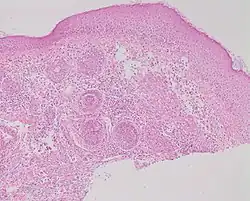

Studies of rosacea and Demodex mites have revealed that some people with rosacea have increased numbers of the mite,[14] especially those with steroid-induced rosacea. Demodex folliculitis (demodicidosis, also known as "mange" in animals) is a condition that may have a "rosacea-like" appearance.[17]

A 2007, National Rosacea Society-funded study demonstrated that Demodex folliculorum mites may be a cause or exacerbating factor in rosacea.[18] The researchers identified Bacillus oleronius as a distinct bacterium associated with Demodex mites. When analyzing blood samples using a peripheral blood mononuclear cell proliferation assay, they discovered that B. oleronius stimulated an immune system response in 79 percent of 22 patients with subtype 2 (papulopustular) rosacea, compared with only 29% of 17 subjects without the disorder. They concluded, "The immune response results in inflammation, as evident in the papules (bumps) and pustules (pimples) of subtype 2 rosacea. This suggests that the B. oleronius bacteria found in the mites could be responsible for the inflammation associated with the condition."[18]